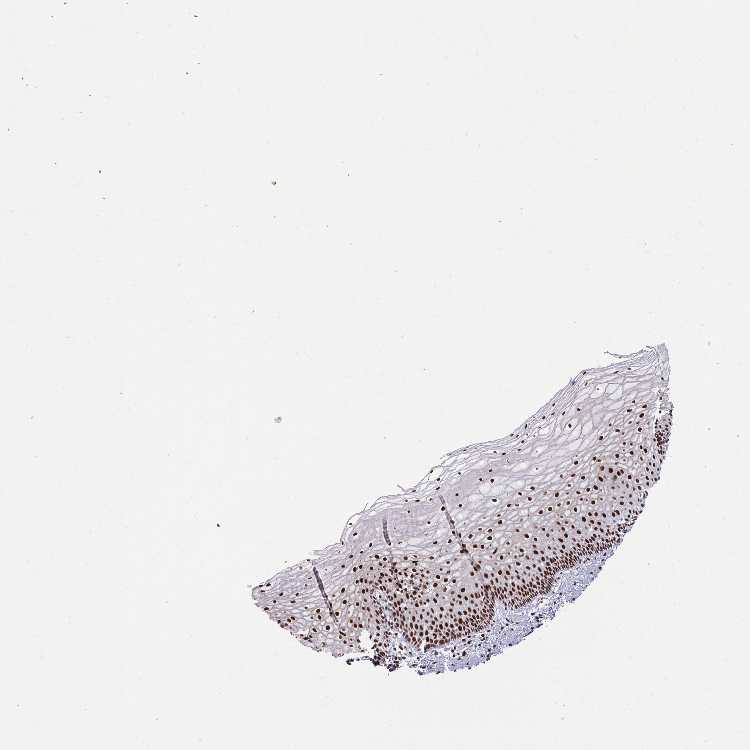

CERVIX - Antibody stainingi

Antibody staining in the annotated cell types in the current human tissue is reported as not detected, low, medium, or high, based on conventional immunohistochemistry profiling in selected tissues. This score is based on the combination of the staining intensity and fraction of stained cells.

Each image is clickable and will lead to virtual microscopy that enables deeper exploration of all samples and also displays staining intensity scores, fraction scores and subcellular localization as well as patient and tissue information for each sample.

Antibody HPA035578

Glandular cells High

Squamous epithelial cells High